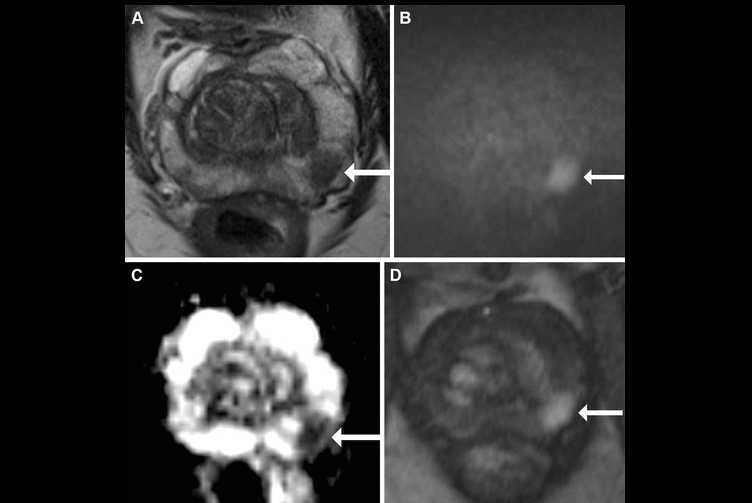

In-bore MRI-targeted biopsy is a highly effective method for grading the severity of prostate cancer, as it enables precise needle placement. Yet whether the cancer grading from the in-bore biopsy matches the final grading determined after surgery, and what factors affect how well these grades match, is underexplored, the authors explained.

To that end, they evaluated factors affecting the detection rate of prostate cancer in patients who underwent in-bore MRI-targeted biopsy and their influence on histologic concordance between biopsy grade group and surgical grade group.

According to the analysis, detection rates for grade group (GG) 2 or higher prostate cancer depended on the size of the MRI target lesion and the Prostate Imaging Reporting and Data System, or PI-RADS, category. Concordance between biopsy and surgical GGs was moderate (60.2%), with a risk of undergrading, the researchers reported.

In-bore MRI-targeted prostate biopsy detection rates were higher for larger lesions (> 10 mm and PI-RADS category ≥ 4).

The concordance between in-bore biopsy and surgical GG was higher when biopsy grades were GG 2 or 3 but lower when they were GG 1, 4, or 5.